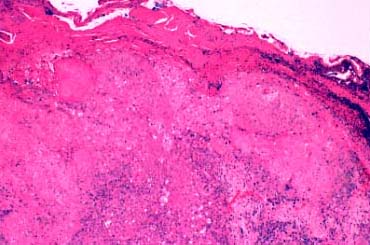

Squamous Cell Carcinoma = الكارسينوما شائكة الخلايا